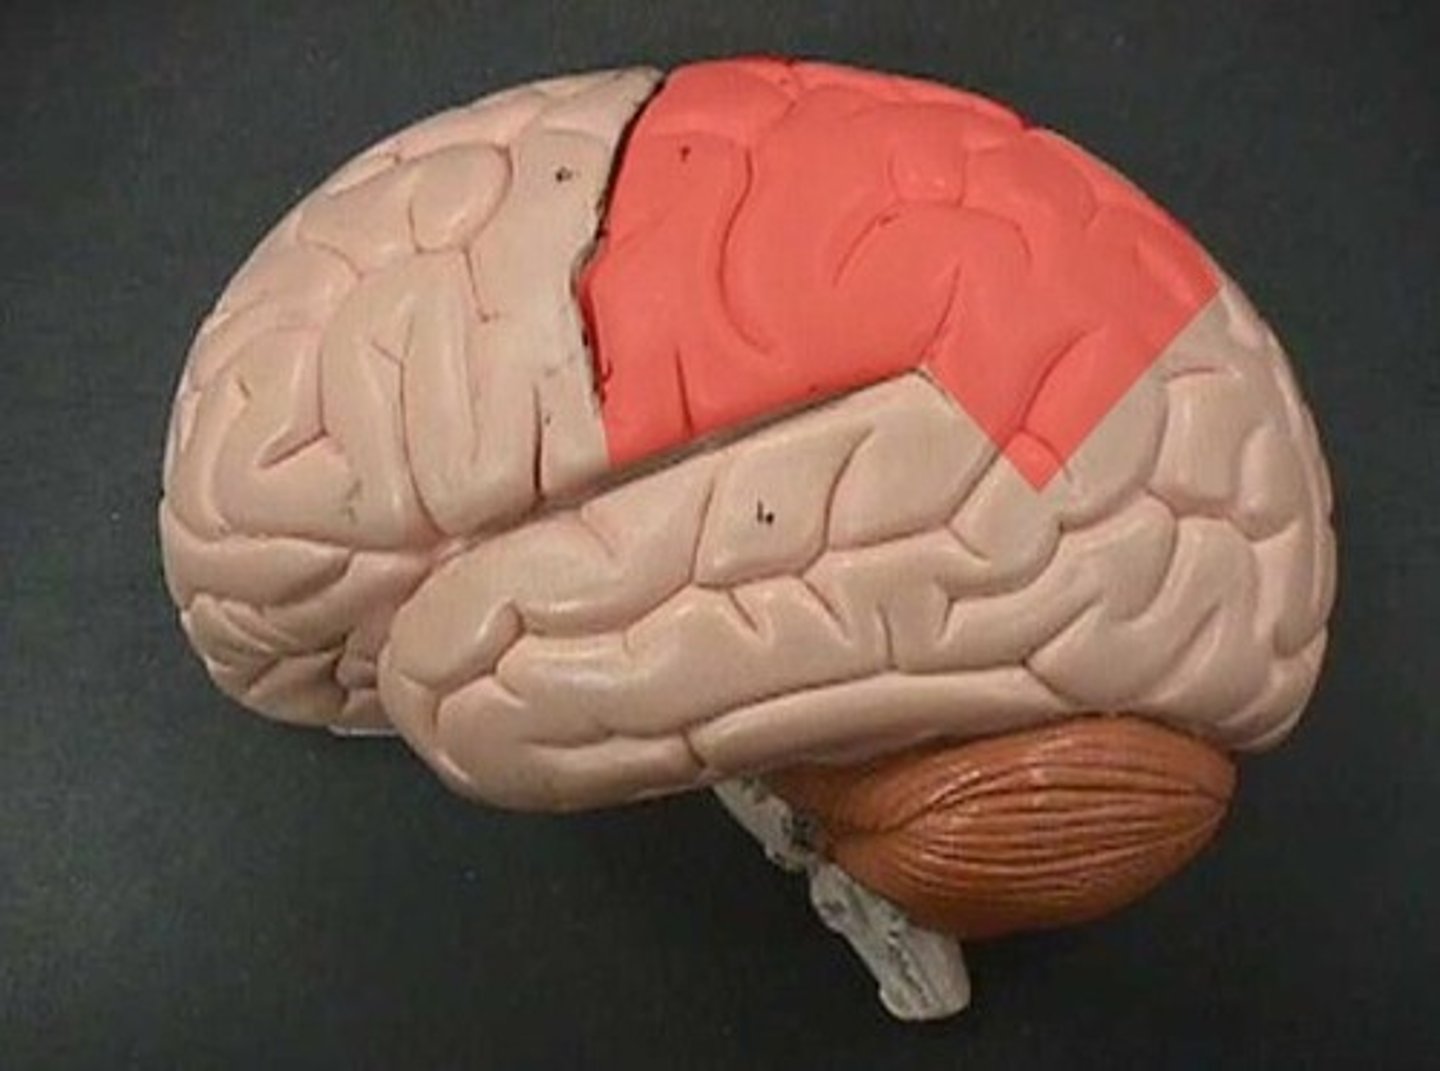

Parietal lobe

receives and processes sensory input for touch and body position